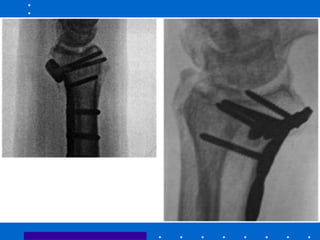

Fixação interna - Placa dorsal

• Vantagens:

• abordagem evita estruturas neurovasculares

palmares

• apoio é no local de compressão da maioria

das fraturas

• Desvantagens:

• tendinite extensores ou ruptura,

particularmente no tubérculo de Lister

• parafusos distais tem de ser orientados

palmar e proximal, isto permite

deslocamento palmar de fragmentos -

incongruência ARUD e mais proeminência

dorsal www.traumatologiaeortopedia.com.br